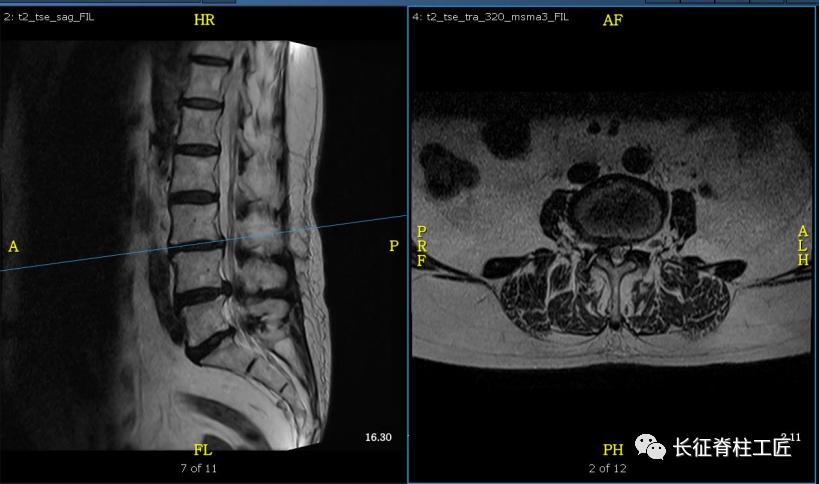

入院检查,腰部疼痛,后伸时加剧,局部压痛,双下肢肌力减退。X线检查,L4、L5骨质增生,MRI显示L4/L5、L5/S1椎间盘突出,马尾神经受压明显,被确诊为腰椎管狭窄症。